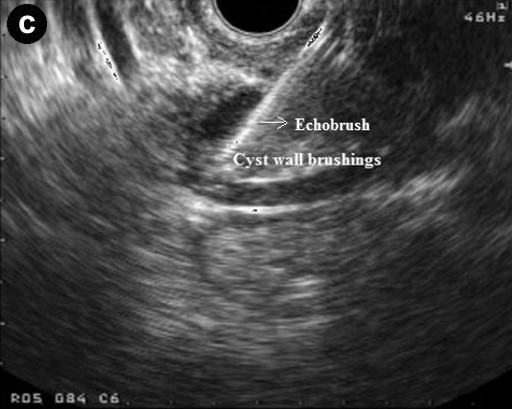

All patients had platelet count and coagulation profile checked and corrected if needed prior to the procedure. Procedures were done under intravenous sedation with diazepam and pethidine or midazolam and fentanyl. Cyst sampling was done by two operators with a combined experience of over 1,000 linear EUS procedures (GPA and KR). The lesion was identified and punctured using a 19 G needle using curvilinear echoendoscope (GF-UCT240-AL5, Olympus KeyMed, Essex, United Kingdom) and 50% of the cyst content was initially aspirated. The echobrush (Cook Medical, Limerick, Ireland, United Kingdom) was then passed through the handle and advanced through the needle till the whole brush could be visualised in the cyst. The wall of the cyst was then brushed by to and fro movement of the brush tip by moving the shaft of the needle at the handle. The opposite wall of the cyst was then visualised by moving the handle of the scope sideways and the brushing repeated at least four times (Figure 1). The brush was targeted if septae or nodules were present on the cyst wall. The brush was pulled back into the needle tip prior to removing the needle from the cyst and the needle apparatus with echobrush was withdrawn as a whole. The cyst was then aspirated to dryness using either a 19 G or 22 G needle. In patients where only FNA was done the cyst was punctured and aspirated using a 22 G needle.

Figure 1. Linear endoscopic ultrasound showing EUS-guided brushing of a cystic pancreatic lesion. a. EUS-FNA 19 G needle entering a cystic lesion in the head of the pancreas. b. The cyst being aspirated. c. The cyst wall being brushed by echobrush introduced through the needle. d. The cyst aspirated to dryness after cyst wall brushing. |